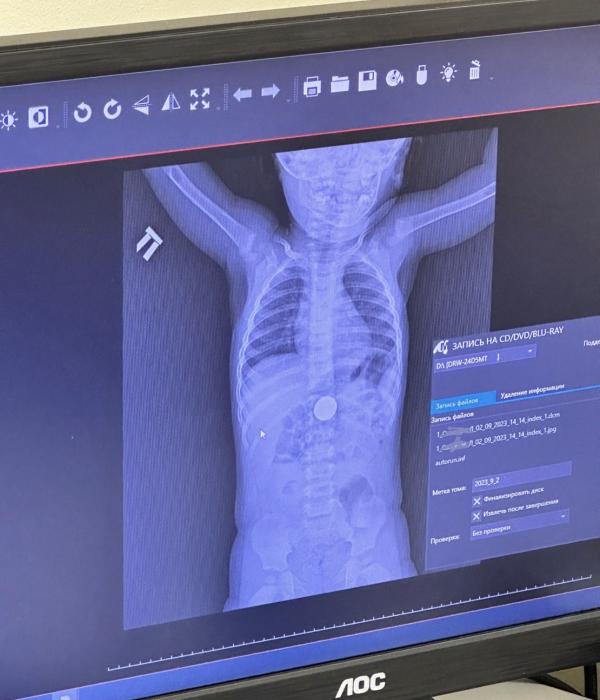

Помчали мы сначала в Зип ( травмпункт детский) сделали нам рентген и отправили на Захарова в детскую, там хирург предложил два варианта : ложиться в палату, под наркозом извлекать монету или ждать три дня, а затем сдаваться

Естественно я согласилась на ждать :)

На следующий день мой мужчинка выкакал эту монетку, счастью моему не было предела.